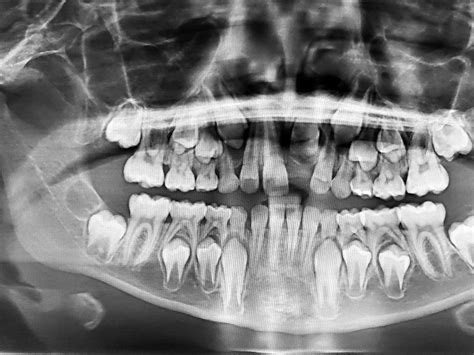

Radiografía dental en niños para diagnóstico y tratamiento.

- Radiografía Panorámica (Ortopantomografía): Ofrece una visión general de toda la cavidad bucal, detectando anomalías como inflamaciones radiculares, tumores y abscesos.

- Radiografía de Aleta de Mordida: Indispensable para el estudio de ortodoncia.